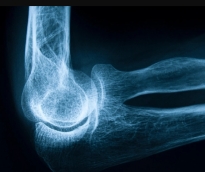

- تسجيل أكثر من 100 حالة لكسور مرتبطة بهشاشة العظام خلال 2023 أكدت مؤسسة حمد الطبية، أهمية توعية أفراد المجتمع بعوامل الخطورة المسببة للإصابة بهشاشة العظام ورفع مستوى الوعي حول أهمية صحة العظام، وتعزيز الكشف والتشخيص المبكر، والتعريف بالتدابير الوقائية للوقاية من هشاشة العظام.. وقد شاركت مؤسسة حمد الطبية في الاحتفال باليوم العالمي لهشاشة العظام تحت شعار»عظام قوية مدى الحياة» والذي يتم الاحتفال به بالتنسيق مع المؤسسة الدولية لهشاشة العظام لتعزيز صحة العظام والتشجيع على اتخاذ الإجراءات الوقائية للحفاظ على صحة العظام خلال جميع مراحل الحياة. من جانبه أشار الدكتور نبيل عبدالله، استشاري المفاصل وأمراض الروماتيزم بمؤسسة حمد الطبية إلى خطورة كسور الورك المرتبطة بهشاشة العظام، حيث تم تسجيل أكثر من 100 حالة في قسم الطوارئ بمستشفى حمد العام خلال عام 2023؛ قائلاً:» يمكن لكسور الورك أن تقلل من قدرة الشخص على التعايش بصورة مستقلة. وقال د. نبيل عبدالله:» أنشأت مؤسسة حمد الطبية عيادات متخصصة تهدف إلى الكشف المبكر عن الكسور المرتبطة بهشاشة العظام وعلاجها، حيث تعتبر عيادة خدمة تجبير الكسور الموجودة بمركز العظام والمفاصل ومستشفى الوكرة في طليعة هذه المبادرات. تركز هذه العيادة على تحديد المرضى الذين يعانون من الكسور جراء الإصابة بهشاشة العظام وضمان حصولهم على العلاج في الوقت المناسب لمنع وقوع مثل هذه الحوادث مستقبلاً. تهدف هذه العيادة من خلال البدء في العلاج مبكراً إلى الحد من مخاطر الإصابة بكسور إضافية بشكل كبير والتي قد تكون مؤلمة وتؤثر على جودة حياة الأفراد». وقال « بالإضافة إلى عيادة تجبير الكسور، تدير مؤسسة حمد الطبية عيادات أمراض الروماتيزم وهشاشة العظام، التي تقوم بفحص وعلاج المرضى المعرضين لخطر الإصابة بهشاشة العظام بصورة استباقية قبل تعرضهم للكسور. تأتي الإحالات إلى هذه العيادات غالباً من أطباء العظام والرعاية الأولية، تتوفر في الوقت الحالي مجموعة متعددة من خيارات علاج هشاشة العظام أكثر من أي وقت سابق إذ ثبت أن العلاجات تقلل من خطر الإصابة بكسور الورك بنسبة تصل إلى 40% وكسور العمود الفقري بنسبة 30 إلى 70%». واضاف أن هشاشة العظام تعتبر حالة تتسم بضعف وترقق العظام مما يزيد من خطر الإصابة بالكسور عند التعرض للحد الأدنى من الإصابات وخاصةً عند كبار السن. وشدد على أهمية الكشف المبكر والتوعية مشيراً إلى أن مرض هشاشة العظام يعرض الأفراد بشكل أكبر لخطر الإصابة بالكسور وخاصة عند كبار السن والنساء. وحول فعاليات الاحتفال باليوم العالمي لهشاشة العظام في مؤسسة حمد الطبية فقد ركزت على التثقيف حول التدابير الوقائية للحماية من الإصابة بهشاشة العظام.

مع التقدم في السن يخشى العديد من الناس إصابتهم بهشاشة العظام، ويشير الأطباء إلى أهمية الوقاية لتفادي الإصابة من هذه الحالة عبر التغذية السليمة. وتسبب هشاشة العظام ضعف العظام وترققها لدرجة أن أي سقوط أو مجهود بسيط مثل الانحناء أو السعال يمكن أن يسبّب كسورًا، وتحدث حالات الكسر المرتبطة بهشاشة العظام بصورة شائعة في الوِرك والرسغ والعمود الفقري، وفق مايو كلينك. وللحفاظ على صحة العظام والوقاية من هشاشتها فإن النظام الغذائي الغني بالكالسيوم يعد مثاليًا، بالإضافة إلى فيتامين د الذي يساعد الجسم على امتصاص الكالسيوم ثم إيداعه في العظام. وتحتاج العظام إلى العناصر الغذائية حتى تتمكن من النمو والحفاظ عليه، ويمكن أن يكون النظام الغذائي الصحي للعظام استراتيجية جيدة لمنع فقدان العظام المستمر، ويجب أن يكون النظام الغذائي جزءا من نمط حياة صحي شامل يتضمن التمارين ومستويات الكالسيوم وفيتامين د المثالية. وإليك خمس عادات من موقعميديكال إكسبرس لتناول الطعام جيدًا من أجل عظام قوية: 1- تناول الخضار والفواكه والحبوب الكاملة تناول المزيد من الخضار والفواكه ُيحسن صحة العظام، لأنها أطعمة منخفضة السعرات الحرارية والدهون بشكل عام، كما أنها غنية بالألياف والفيتامينات والمعادن الأساسية، وتحتوي على مواد كيميائية نباتية، وهي مواد يمكن أن تحمي من الأمراض المختلفة، بما في ذلك هشاشة العظام. وتحتوي الحبوب الكاملة على المزيد من العناصر الغذائية، وخاصة المغنيسيوم والألياف، مقارنة بالحبوب المكررة. 2- اختر مصادر صحية للبروتين والدهون يعد البروتين عنصرا مهما لصحة العظام لأنه مكون رئيسي في أنسجة العظام ويلعب دورا في الحفاظ على العظام، وأفضل الخيارات من البروتينات النباتية هي الفول والمكسرات، وكذلك الأسماك والدواجن منزوعة الجلد واللحوم الخالية من الدهون. وبحسب الدراسات يجب أن يمثل البروتين 25٪ إلى 35٪ من إجمالي السعرات الحرارية اليومية، والبروتينات النباتية غنية بالفيتامينات والمعادن والمركبات النباتية الشبيهة بالإستروجين التي تساعد في الحفاظ على العظام. وتعتبر منتجات الألبان قليلة الدسم، بما في ذلك الحليب والزبادي، مصدرا جيدا آخر للبروتين، وتوفر الكالسيوم الذي يفيد صحة العظام. 3- احصل على الكثير من الكالسيوم الكالسيوم ضروري لصحة العظام وهو لبنة أساسية في بناءها، ويساعد على منع فقدان العظام وكسور هشاشة العظام لدى كبار السن، على الرغم من أن المدخول اليومي الموصى به للبالغين يتراوح عمومًا من 1000 إلى 1200 ملليغرام، فإن النظام الغذائي النموذجي يوفر أقل من ذلك بكثير. منتجات الألبان التقليدية مثل الحليب واللبن والجبن، هي أغنى مصادر الغذاء، على سبيل المثال حصة واحدة من 8 أونصات من الحليب قليل الدسم أو كامل الدسم تحتوي على حوالي 300 ملليغرام من الكالسيوم. ومن المصادر الغذائية الغنية بالكالسيوم ما يلي: • مشتقات الحليب قليلة الدسم • الخضراوات الورقية ذات اللون الأخضر الداكن • السلمون المعلَّب مع العظام والسردين • منتجات الصويا مثل التوفو • حبوب الإفطار وعصير البرتقال المضاف إليهما كالسيوم 4 - الحد من السكر والملح والمضافات الفوسفاتية توفر الأطعمة التي تحتوي على السكريات المضافة أثناء المعالجة عموما الكثير من السعرات الحرارية والمواد المضافة والمواد الحافظة، لكنها تقدم القليل من الفوائد الصحية. ويعد الهدف من تقليل كمية الملح في النظام الغذائي لتسببه بـ زيادة كمية الكالسيوم التي يفرزها الجسم عند التبول. ويستخدم الفوسفور كمادة مضافة في العديد من الأطعمة المصنعة، يمكن أن يتداخل الكثير من الفوسفور في النظام الغذائي مع كمية الكالسيوم التي يتم امتصاصها من خلال الأمعاء الدقيقة. 5- التخفيف من استهلاك الكافيين يزيد الكافيين بشكل طفيف من فقدان الكالسيوم أثناء التبول، لكن الكثير من تأثيره الضار المحتمل ينبع من استبدال المشروبات التي تحتوي على الكافيين بالحليب والمشروبات الصحية الأخرى، ويعد الاستهلاك المعتدل للكافيين حوالي كوبين إلى ثلاثة أكواب من القهوة يوميا غير ضار طالما أن نظامك الغذائي يحتوي على الكالسيوم الكافي.

أطلقت مؤسسة حمد الطبية حملة توعوية عامة حول مرض هشاشة العظام بهدف حث كافة أفراد المجتمع على إجراء الفحوص والتحاليل اللازمة للتأكد من عدم إصابتهم بالمرض الذي يتسبب في ضعف واضمحلال الكتلة العظمية بالجسم. وتأتي هذه الحملة بمناسبة اليوم العالمي لمرض هشاشة العظام حيث بدأت الفعاليات التوعوية في مستشفى الخور ومستشفى الوكرة على أن تقام أنشطة مماثلة في مستشفى حمد العام الأسبوع المقبل. كما ينظم قسم أمراض الروماتيزم بمؤسسة حمد الطبية يوم الأحد المقبل ندوة للحديث حول الشعار الذي تم اختياره للاحتفال باليوم العالمي لهشاشة العظام 2015 وهو "اخدم عظامك لتصبح أقوى" وتتحدث فيها الدكتورة نادية العلي استشاري ورئيس قسم الغدد الصماء وأمراض التمثيل الغذائي بالمستشفى الأميري في دولة الكويت. ويحتفل العالم باليوم العالمي لمرض هشاشة العظام بتاريخ 20 أكتوبر من كل عام وذلك من خلال إطلاق حملة توعوية تتواصل فعالياتها طوال العام وتهدف إلى زيادة الوعي حول الوقاية والتشخيص والعلاج لمرض هشاشة العظام وخلافه من أمراض العظام الاستقلابية. وتركز حملة مؤسسة حمد على أهمية الحفاظ على نظام غذائي صحي لحماية العظام في مرحلة الشباب حتى بلوغ سن متقدم حيث يركز شعار اليوم العالمي لمرض هشاشة العظام هذا العام على ضرورة الالتزام بغذاء يعزز بنية العظام لدى الإنسان ويمنع الإصابة بهشاشة العظام فيما بعد. وقالت الدكتورة سمر العمادي استشاري أول في قسم أمراض الروماتيزم بإدارة الباطنية بمؤسسة حمد الطبية وممثلة قطر في اتحاد الجمعيات العربية لهشاشة العظام إن الوقاية من مرض هشاشة العظام خير من علاجه حيث ان الوقاية تعتمد على الكشف المبكر وتغيير نمط الحياة من خلال زيادة معدل التعرض لضوء الشمس والمواظبة على ممارسة التمارين الرياضية فضلا عن اجتناب تعاطي الكحول والإقلاع عن التدخين. وأشارت إلى أنه خلال الحملة سيتم تثقيف المرضى ومراجعي العيادات الخارجية من خلال توزيع مطويات تشتمل على معلومات حول مرض هشاشة العظام وأعراضه وطرق تشخيصه وعلاجه حيث سيتواجد عدد من مثقفي المرضى وأطباء الروماتيزم للإجابة على الأسئلة والاستفسارات التي يطرحها الجمهور. وأوضحت الدكتورة سمر أن مرض هشاشة العظام يؤدي إلى جعل العظام ضعيفة وسهلة التكسر حيث إن مجرد سقطة أو حتى بعض الحركات الطفيفة مثل الانحناء أو السعال قد تتسبب في كسر العظام وعادة ما تحدث الكسور الناتجة عن هشاشة العظام في الورك أو المعصم او العمود الفقري. ولفتت إلى وجود نوعين من هذا المرض هما هشاشة العظام الأولية (ما بعد سن اليأس أو الشيخوخة) وهشاشة العظام الثانوية وقد تحدث هشاشة العظام بسبب بعض التغيرات الهرمونية ونوعية الأطعمة التي يتناولها الإنسان وعدم التعرض لضوء الشمس كما أن المرض ربما يكون له صلة ببعض أمراض الكلى..كما توجد أسباب أخرى للمرض مثل سوء امتصاص الكالسيوم وفيتامين (د) من الأمعاء والاضطرابات الهرمونية (فرط نشاط جنيبات الدرقية والتسمم الدرقي) وتعاطي بعض الأدوية مثل الأدوية المضادة للصرع وأقراص الكورتيزون الموصوفة لأشخاص مصابين بالتهاب المفاصل الروماتزمي أو الربو أو بعض الأمراض الجلدية.